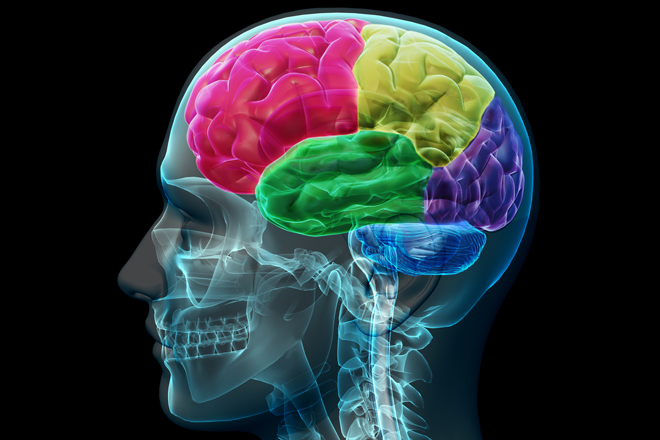

El TDAH es un problema del cerebro, no de conducta

Según un estudio, las personas con trastorno de déficit de atención e hiperactividad tienen el cerebro ligeramente más pequeño.

Según un estudio, las personas con trastorno de déficit de atención e hiperactividad tienen el cerebro ligeramente más pequeño.